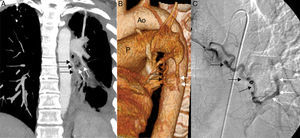

We report the case of a 31-year-old patient with a history of advanced HIV infection (stage C3) with poor therapeutic control, consulting due to hemoptysis. Chest radiograph revealed sequelae from a tuberculosis lung infection involving the left hemithorax in particular. Chest CT angiogram identified a fistula between tortuous, dilated branches of the left bronchial artery and a filiform segmental branch of the left lower lobe pulmonary artery (Fig. 1A and B). Angiogram confirmed the existence of this fistula (Fig. 1C), and embolization was subsequently performed.

(A) Coronal maximum intensity projection (MIP) reconstruction of CT showing a communication between the tortuous branches of the left bronchial artery (black arrows) and a filiform segmental branch (white arrows) of the left lower lobe artery. Note sequelae from tuberculosis in the left hemithorax. (B) 3D reconstruction (volume rendering) of chest CT (Ao: aorta; P: pulmonary artery) providing a better view of the fistula between the branches of the left bronchial artery (black arrows) and the pulmonary artery (white arrows). (C) Angiogram showing retrograde filling of pulmonary arteries (white arrows) from the tortuous branches of the left bronchial artery (black arrows).